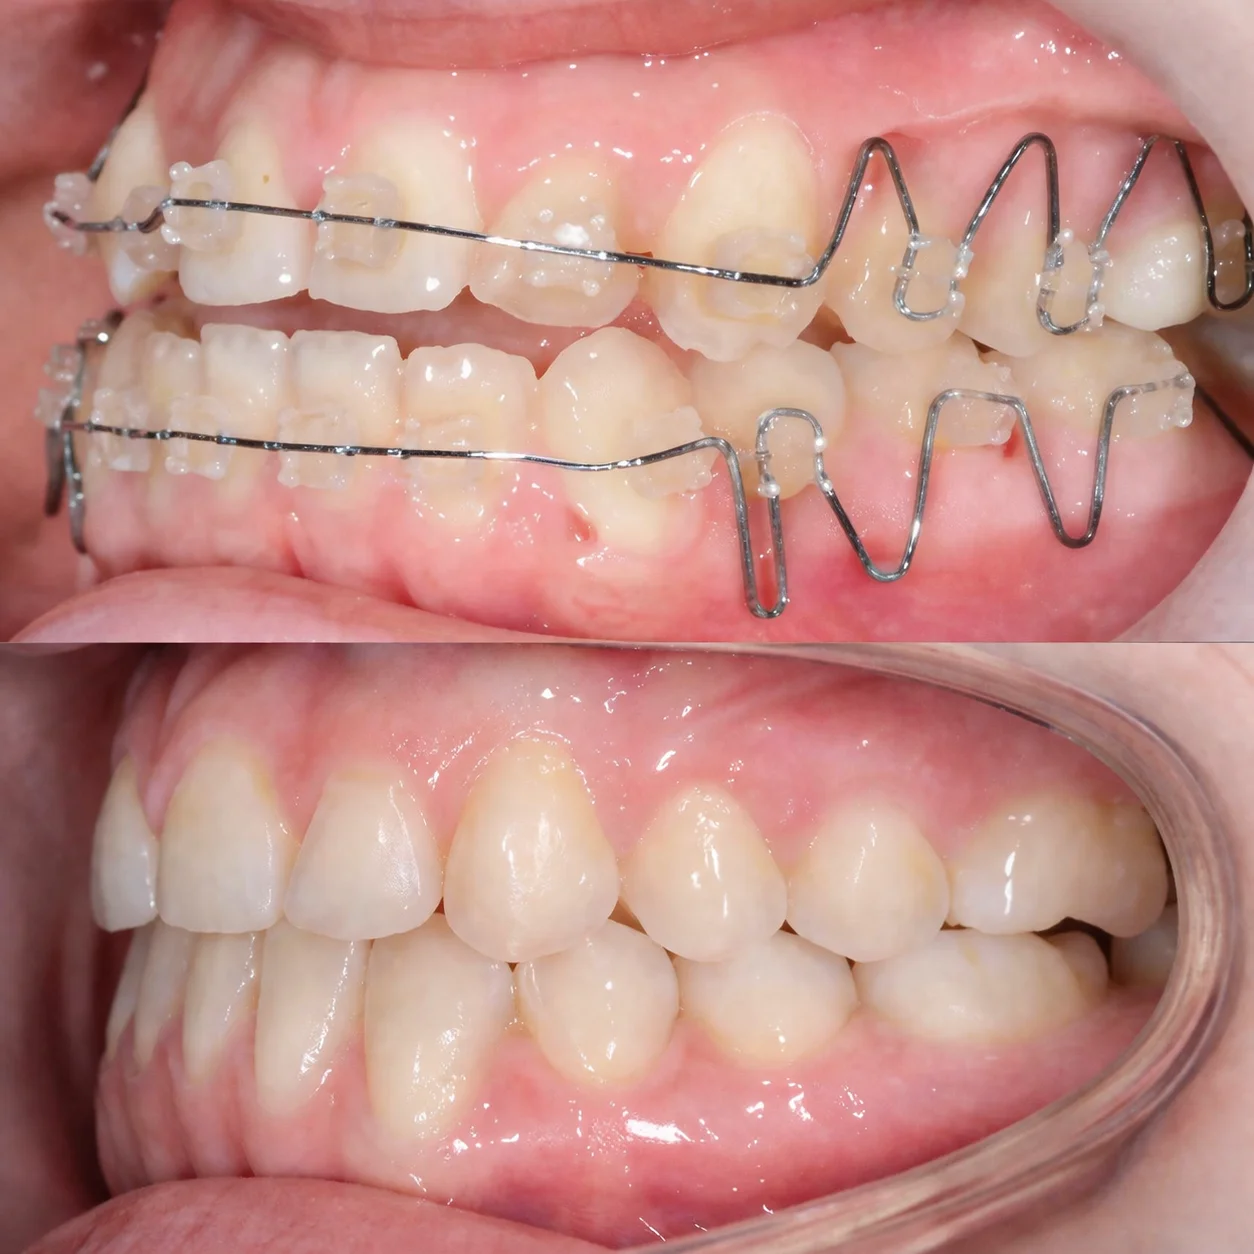

Efekty leczenia

Aparat ortodontyczny

Sięgamy po nie wtedy, gdy potrzebne są poważniejsze zmiany — praca ze zgryzem, stawem i całym układem. Jeśli masz dyskomfort, trzaski w stawie, napięcie mięśni, bóle głowy albo uszu, takie przypadki najlepiej rozwiązywać aparatem